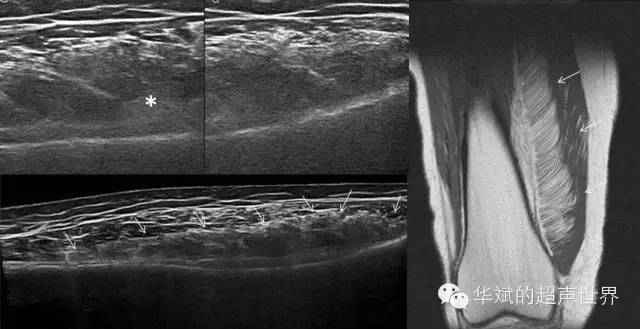

肌间浸润性脂肪瘤可以渗透于骨骼肌纤维和基质之间,形成有条纹的外观。最常见的位置是下肢(45%)、躯干(17%)、肩部带肌(12%)和上肢(10%)。

超声检查显示肌肉内沿肌肉纤维浸润分布的高回声包块,病变常常界限不清,但通常都局限于一块肌肉内,不会突破肌肉的筋膜。由于病变内部界面增多,后方常常伴有回声的衰减,病变的长轴通常平行于肌肉纤维。

肌内浸润脂肪瘤也可能包含其他间充质成分,尤其是纤维结缔组织,这是病变的回声更为复杂。MRI能够清晰显示浸润于肌纤维间隙内的脂肪组织对肌纤维并没有破坏。

图1 肌间浸润性脂肪瘤。大腿外侧股内侧肌内的包块。右图为T1加权MR成像。